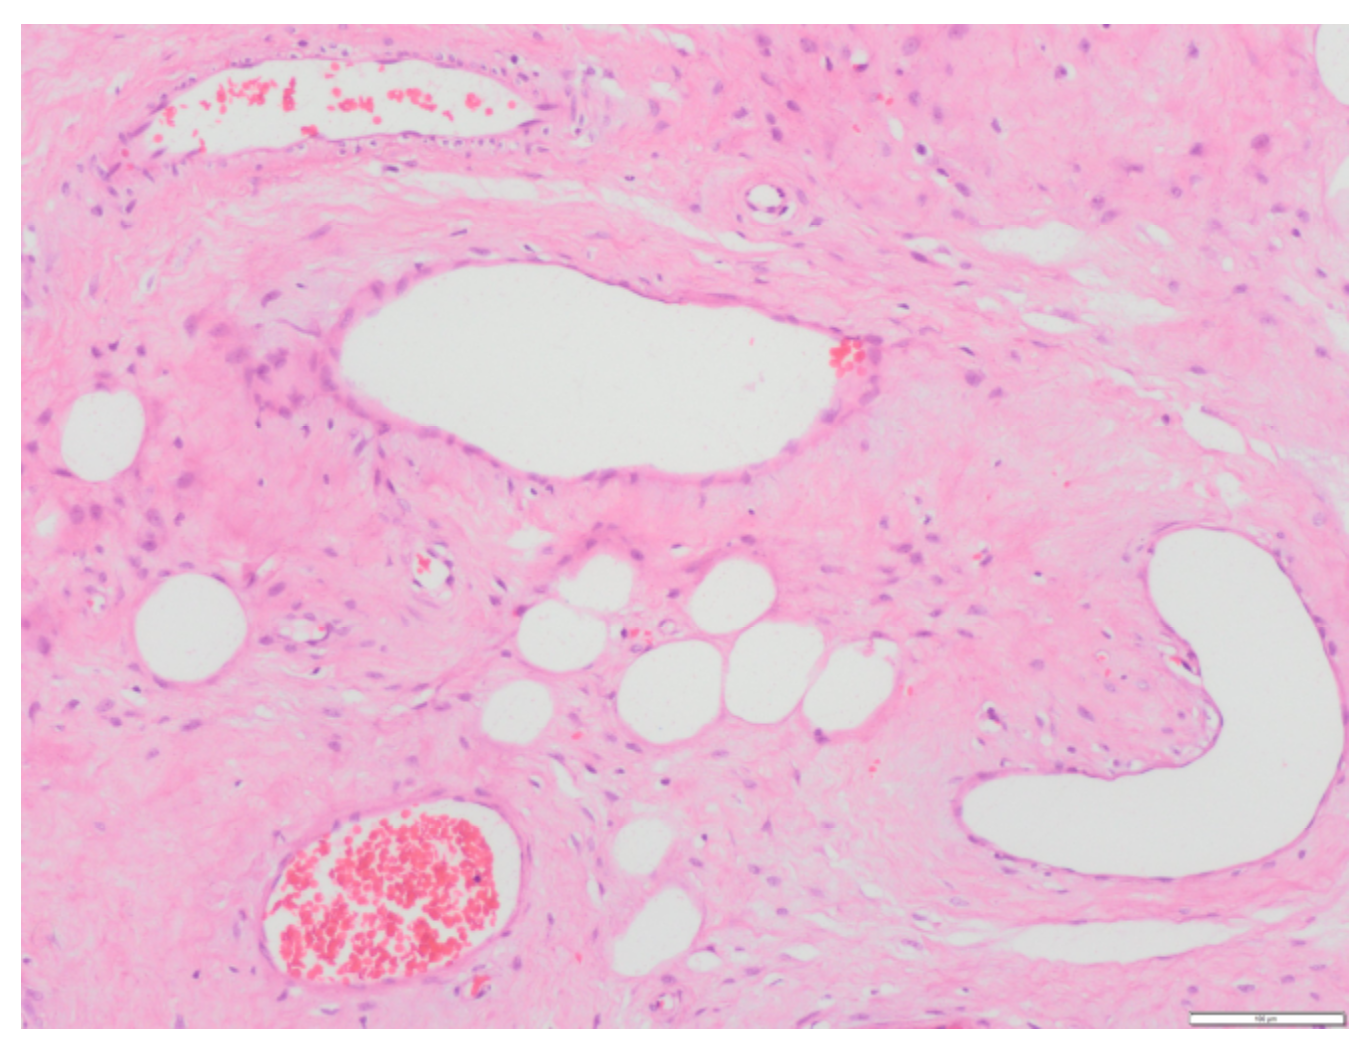

The ultrasound examination at week 20 found fetal findings within normality, with female fetal sex. The previously described tumors were visualized without changes in terms of measurements and ultrasound characteristics. The Doppler of the uterine arteries was pathological, so a follow-up was scheduled at week 26. A magnetic resonance imaging (MRI) of the pelvis was requested which described, in addition to the already known and stable lesions, a complex tumor located in the 7 × 3 × 3.5 cm vesico-vaginal space that suggested the presence of a pedunculated myoma from the cervix as a diagnostic option (Figure 1 and Figure 2).

The most appropriate imaging tests for the study of this type of lesion are ultrasound 146 and MRI. At resonance, they present a laminated pattern in T2. In T1, alternating hyper and hypointense linear areas are seen. Rarely, cystic degeneration or intratumoral vessels are seen. In the present case, both complementary tests were performed. Computed tomography is generally used as an extension study and, in the case of our patient, it was negative [2,12].

Figure 2. MRI (Magnetic Resonance Imaging) images during pregnancy: * Angiomyxoma (a) Sagittal section of the MRI; (b) Axial section of the MRI; and (c) Coronal Section of the MRI.